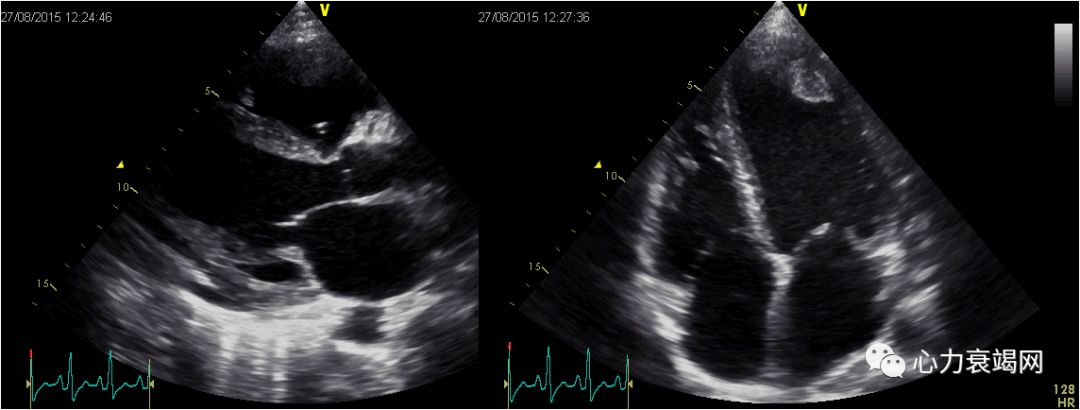

女,16岁。反复发热4年,活动后胸闷气短7月

ANA、抗Sm抗体、抗nRNP及抗SSA均阳性,LA(++++),白细胞降低,严重血小板降低,最低至30×109/L ,诊断“系统性红斑狼疮” 。

7个月前左心衰症状:开始出现快步走后即觉胸闷、憋气, 及突发夜间不能平卧。上二楼即感呼吸困难

外院ECHO:扩张型心肌病,左房、左室扩大,左室舒张、收缩功能降低,二尖瓣少量返流,EF27- 45%。

节段性运动异常

治疗前

2个月后